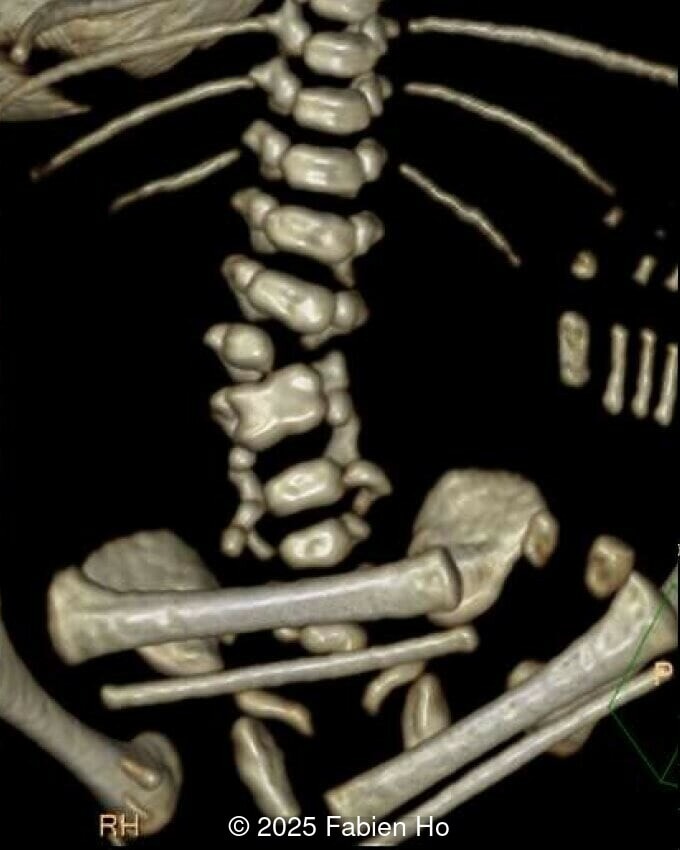

At 36 weeks gestation, the abdominal findings were unchanged however, the bones appeared short (<1st percentile) and the spine had an unusual appearance, therefore a computed tomography was performed at 37 weeks gestation.

• Short long bones (<1st percentile), normal mineralization, and no sign of lethal chondrodysplasia

• Dysostosis: Hemivertebrae L3, fused L4-L5, abnormal left foot with short metatarsals and missing phalanges